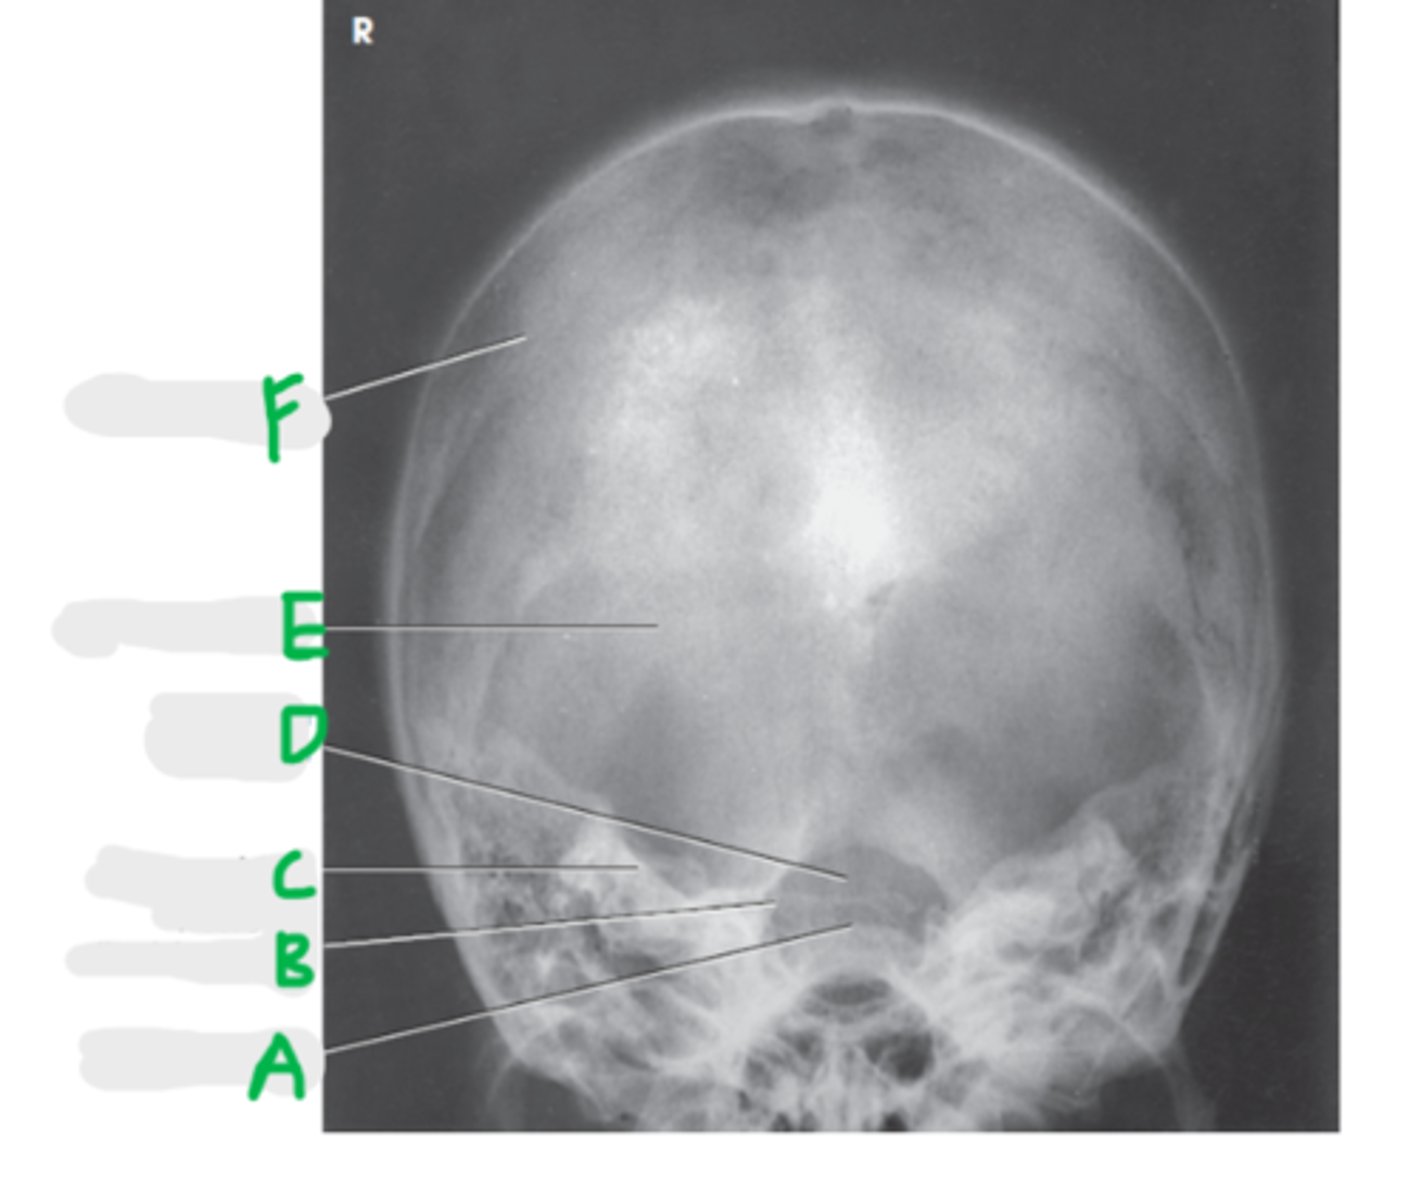

Coronal Suture

A

Orbital roof

B

Sella turcica

C

Sphenoid sinus

D

Petrous portion of temporal bone

E

Temporomandibular joint

F (jt)

EAM

G

Mandibular rami

H

Lateral Skull

What projection is this?

CR 2 inches superior to EAM

What is the CR for a lateral skull?

Interpupillary line (IPL)

What line is perpendicular to the IR for a lateral skull?

IOML and MSP

What line is parallel to the IR?

BOTH!

What lateral do we do for a skull?